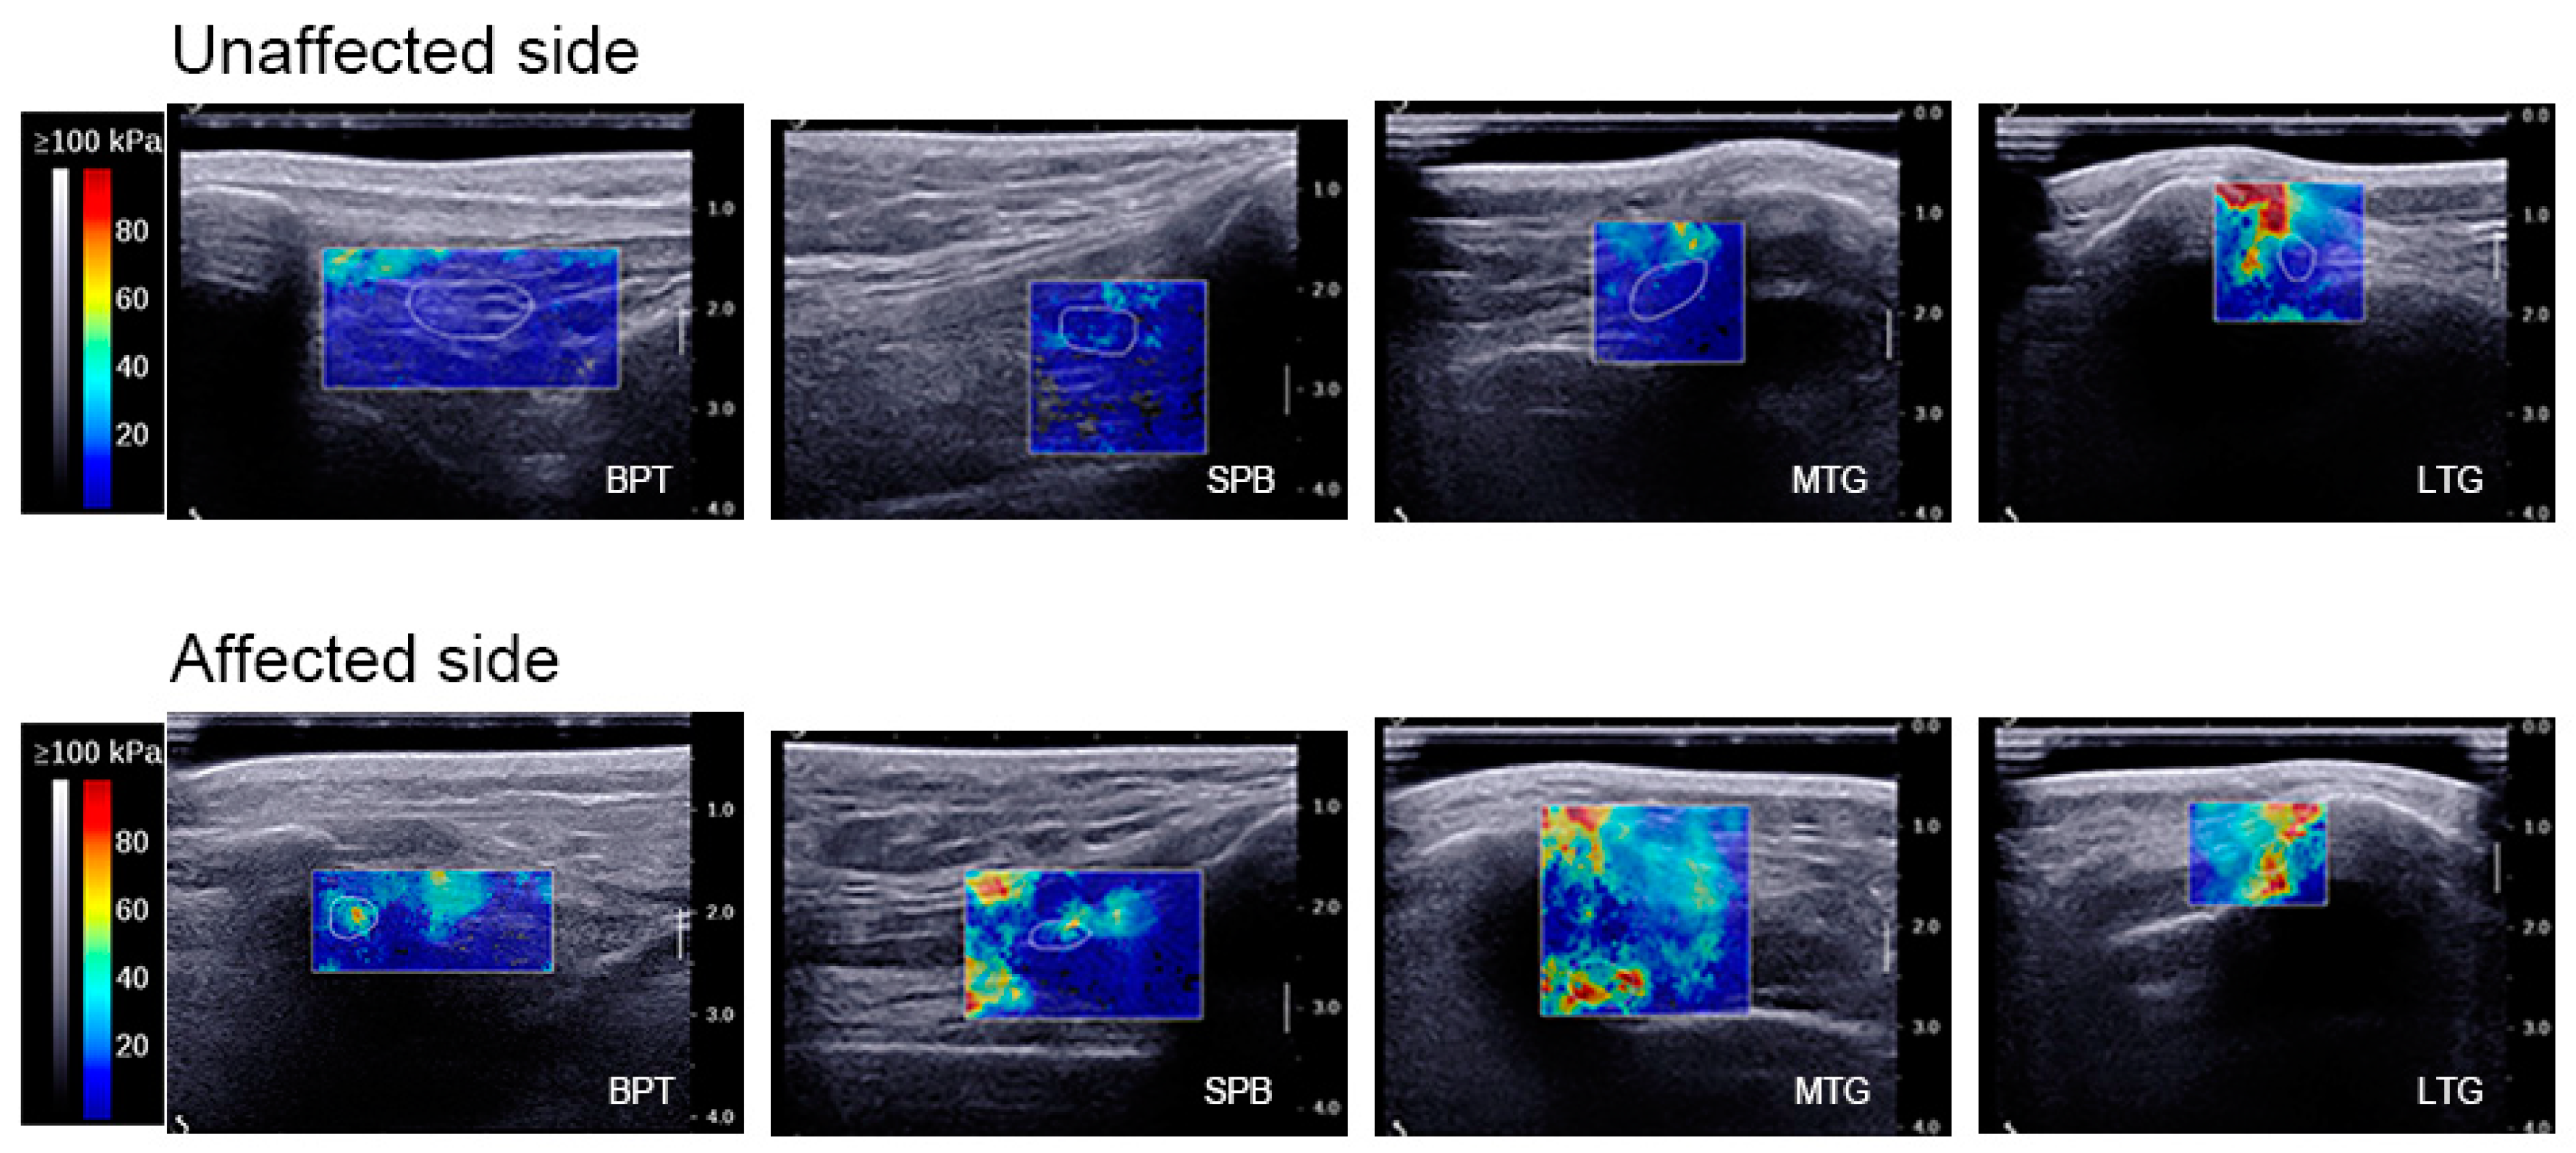

| SWE values of BPT (kPa) | 0° KF | 16.04 ± 11.84 | 34.04 ± 11.52 |

| 30° KF | 17.13 ± 13.75 | 39.41 ± 18.38 | |

| 60° KF | 26.76 ± 21.96 | 68.63 ± 33.63 | |

| 90° KF | 30.46 ± 23.51 | 122.93 ± 42.50 | |

| SWE values of the SPB (kPa) | 0° KF | 21.35 ± 12.96 | 28.21 ± 11.41 |

| 30° KF | 29.00 ± 10.81 | 51.49 ± 19.96 | |

| 60° KF | 41.44 ± 29.32 | 98.74 ± 47.27 | |

| 90° KF | 47.52 ± 16.18 | 108.32 ± 45.25 | |

| SWE values of the MTG (kPa) | 0° KF | 25.98 ± 13.90 | 39.57 ± 14.80 |

| 30° KF | 25.92 ± 7.30 | 53.62 ± 18.58 | |

| 60° KF | 36.06 ± 13.88 | 72.60 ± 30.68 | |

| 90° KF | 41.05 ± 13.65 | 85.58 ± 20.40 | |

| SWE values of the LTG (kPa) | 0° KF | 34.68 ± 15.24 | 55.82 ± 20.93 |

| 30° KF | 48.25 ± 26.16 | 81.77 ± 31.97 | |

| 60° KF | 56.34 ± 25.12 | 94.92 ± 34.93 | |

| 90° KF | 64.00 ± 31.86 | 107.19 ± 35.71 | |